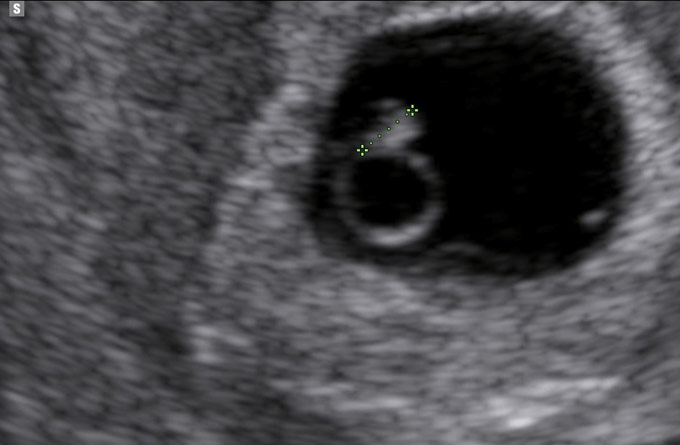

An early pregnancy scan is beneficial for confirming pregnancy location and providing an accurate estimation of gestational age, which is crucial for ensuring appropriate ante-natal care and monitoring your baby’s development.

Hopefully, you will be far enough along, and you will be able to see your baby’s heartbeat and it will give you an opportunity to say ‘hello!’ to your little one for the first time.

Whether you are looking to confirm a pregnancy, determine the gestational age and establish an idea of Estimated Due Date (EDD), the Baby Scantastic team can help to alleviate any worries you may be having in these early days.

This enables us to do a baseline scan to establish that the pregnancy is in the correct location, and identify gestational age if possible.

We then offer a further follow-up scan to reassure our new parents that there has been appropriate development to confirm a viable ongoing pregnancy and give an estimation of gestational age.

If you are certain, you are over 8 weeks then the dating scan will also confirm the pregnancy is in the correct location and give an estimation of gestational age. If you are less than 6 weeks and we are unable to confirm baby’s heartbeat you will be required to upgrade to the early pregnancy bundle.